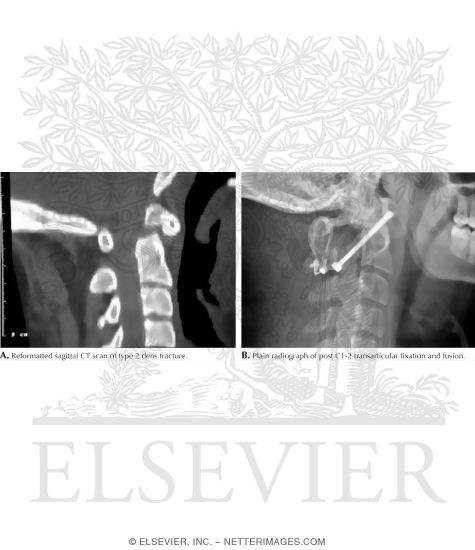

Dens Fracture of Cervical Spine